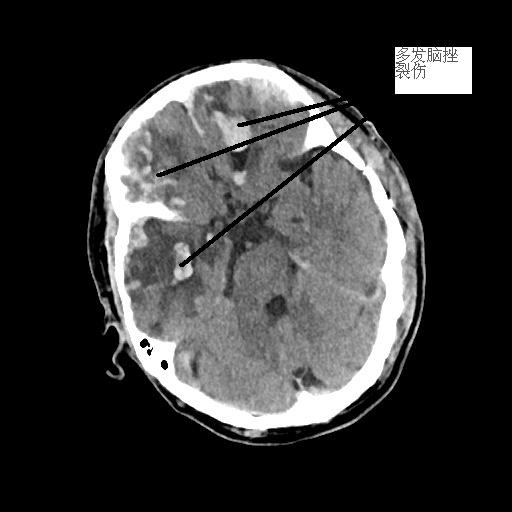

患者潘先生,因騎車摔倒入院搶救。入院時(shí),潘先生神志已模糊,無法對(duì)答,檢查檢驗(yàn)提示顱內(nèi)多發(fā)損傷,出現(xiàn)腦疝,病情危重,我院神經(jīng)外科團(tuán)隊(duì)緊急聯(lián)系福醫(yī)大附二院當(dāng)日值班專家來院開展開顱手術(shù)。經(jīng)及時(shí)搶救,患者病情穩(wěn)定,轉(zhuǎn)危為安。

<<<< 治療前后對(duì)比